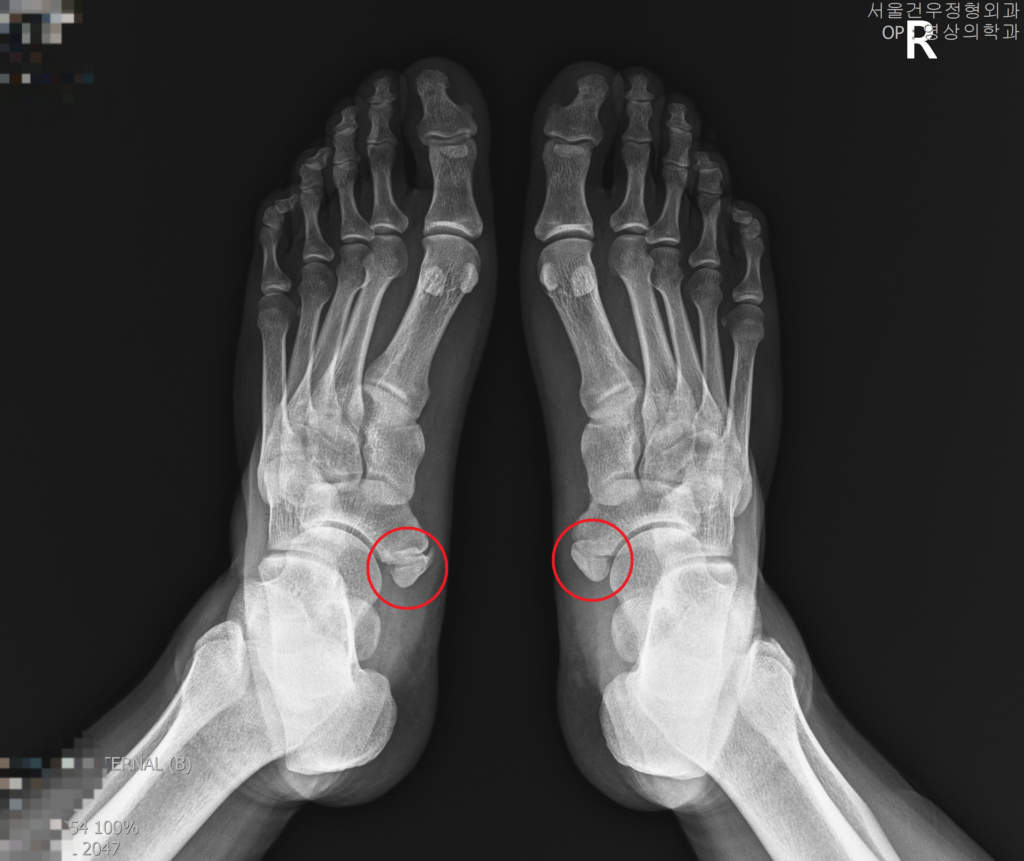

부주상골증후군치료: 수술적 대비 비수술적 치료 방법 비교

부주상골 증후군은 척추의 경추 부위에 있는 부주상골 신경의 염증으로 인해 발생하는 통증을 의미합니다. 이 질환은 일상생활에 지장을 주는 만성통증을 유발하며, 적절한 치료가 필요합니다. 부주상골증후군의 치료에는 수술적 방법과 비수술적 방법이 있으며, 환자의 상태와 증상에 따라 적합한 치료 방법을 선택해야 합니다.